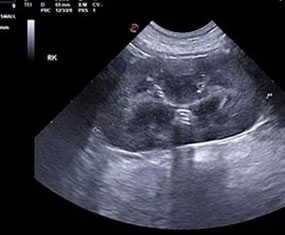

We elected to offer not only abdominal, cardiac and small parts ultrasound but also provide interventional procedures necessary to fulfill the diagnostic pathway. By doing so, we are capable of scanning a patient, working with attending veterinarians to assess patients for biopsy or aspiration and then collecting any samples that may be required to accurately diagnose and address the underlying concern.

At RVUS we have chosen industry leading equipment from vendors with reputable and proven track records in the industry. From the front lines to your final report it is imperative that the equipment and the user provide images that equip the specialists with the highest level of quality and reproducibility to confidently provide an accurate interpretation of the sonogram.

This, in turn, provides you with additional tools to arrive at a diagnosis and prognosis and to enhance the care model for your patient and confidence with your client. Our team of professionals with decades of ultrasound experience encourage the use of ultrasound as a leading route to non-invasively assess organs and pathology in question. To cover that spectrum, a variety of transducers are essential, all with different characteristics.

Whether your patient is 100 lbs or 10 lbs, take comfort in knowing your sonographer is capable of generating images that are sensitive and specific to the clinical concerns.